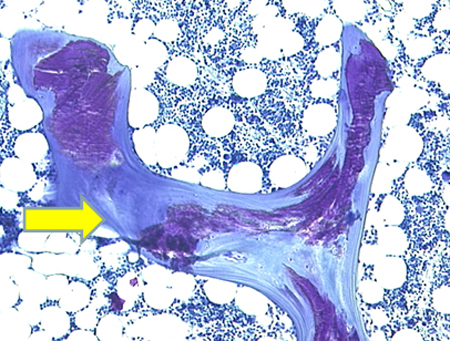

Osteomalácia

Fotomicrografia de biópsia óssea transilíaca de um paciente com osteomalácia demonstrando osteoide desmineralizado (mostrado em roxo). A largura dos osteoides é aumentada substancialmente

Do acervo de Bridget Sinnott, MD; usado com permissão